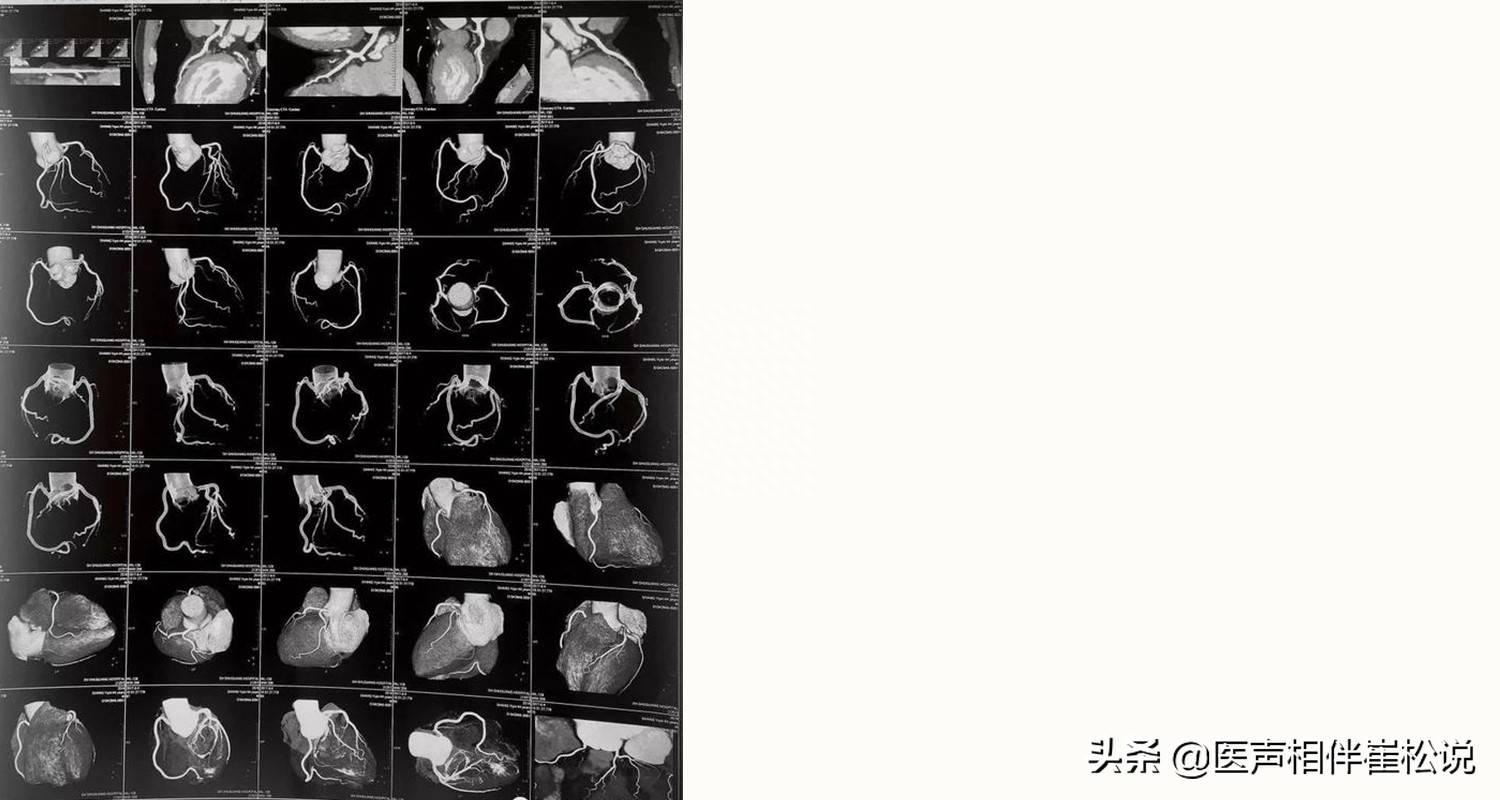

那么我们接着做“冠状动脉CT造影”,对阴性的预测价值非常高,适于筛查!如果做出来没问题,那就说明不是心肌血!!!

冠脉CTA图像